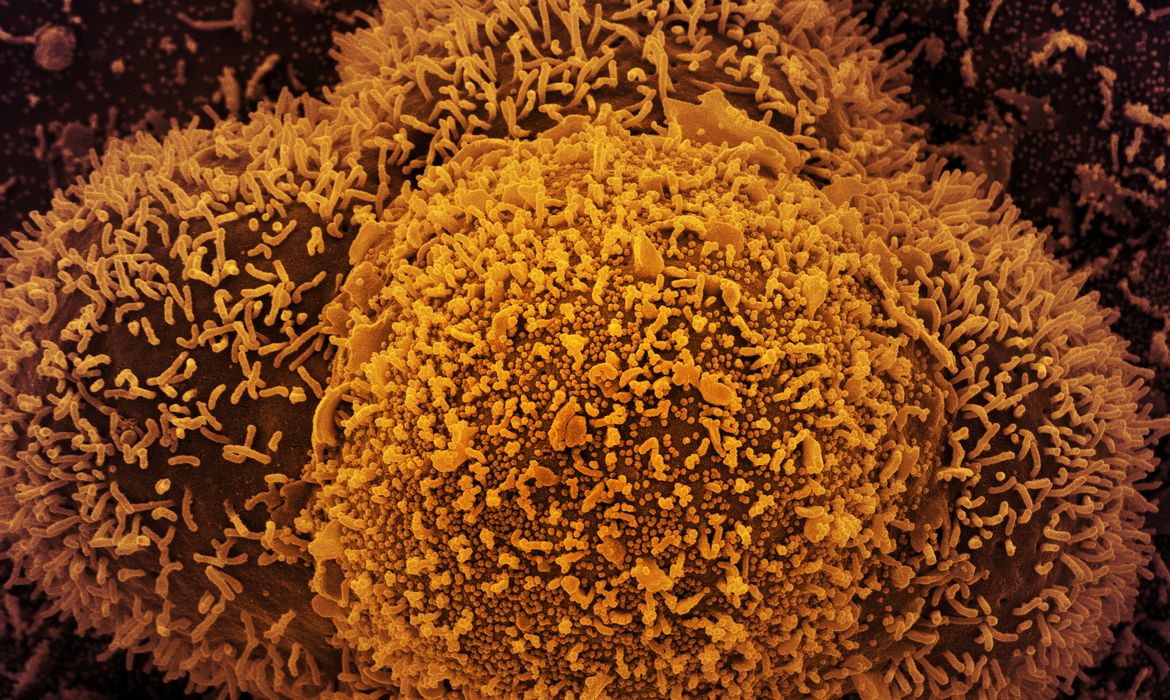

Segundo o estudo, publicado na plataforma BioRxiv e que ainda aguarda revisão pelos pares, a velocidade de reprodução da BA.2 é 1,4 vezes maior que a verificada para a primeira linhagem da Ômicron. Com base em dados epidemiológicos de vários países, os investigadores descobriam que, em comparação à versão original, a BA.1 apresenta mais de 50 diferenças na estrutura viral, o que equivale a praticamente o dobro das mutações que existiam entre a Delta e a primeira forma de coronavírus.